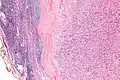

| Micrograph of an intranodal palisaded myofibroblastoma. H&E stain. | |

IPMs are diagnosed by examination of the tissue by a pathologist. They have a rim of peripheral lymphoid tissue (remnant of a lymph node) and consist of spindle cells with nuclear palisading. Red blood cell extravasation is common and blood vessels surrounded by collagen with (fine) peripheral spokes (amianthoid fibers) are usually seen.[2]

Immunostains for smooth muscle actin and cyclin D1 are characteristically positive. The main histologic differential diagnosis is schwannoma.

Low mag. -